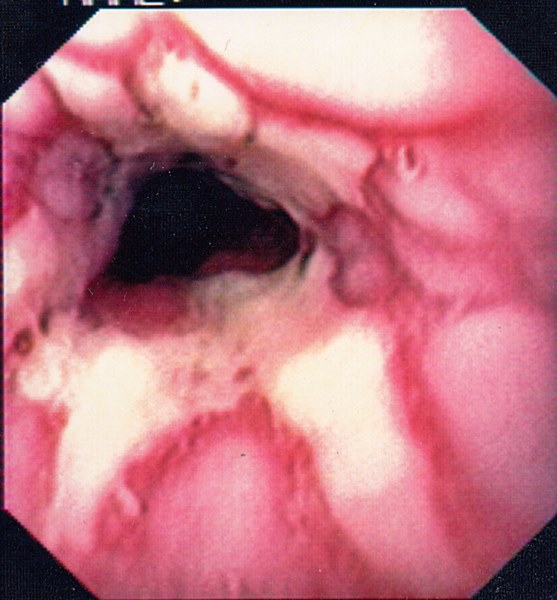

Reflux Oesophagitis Grade D (Los Angeles Classification)